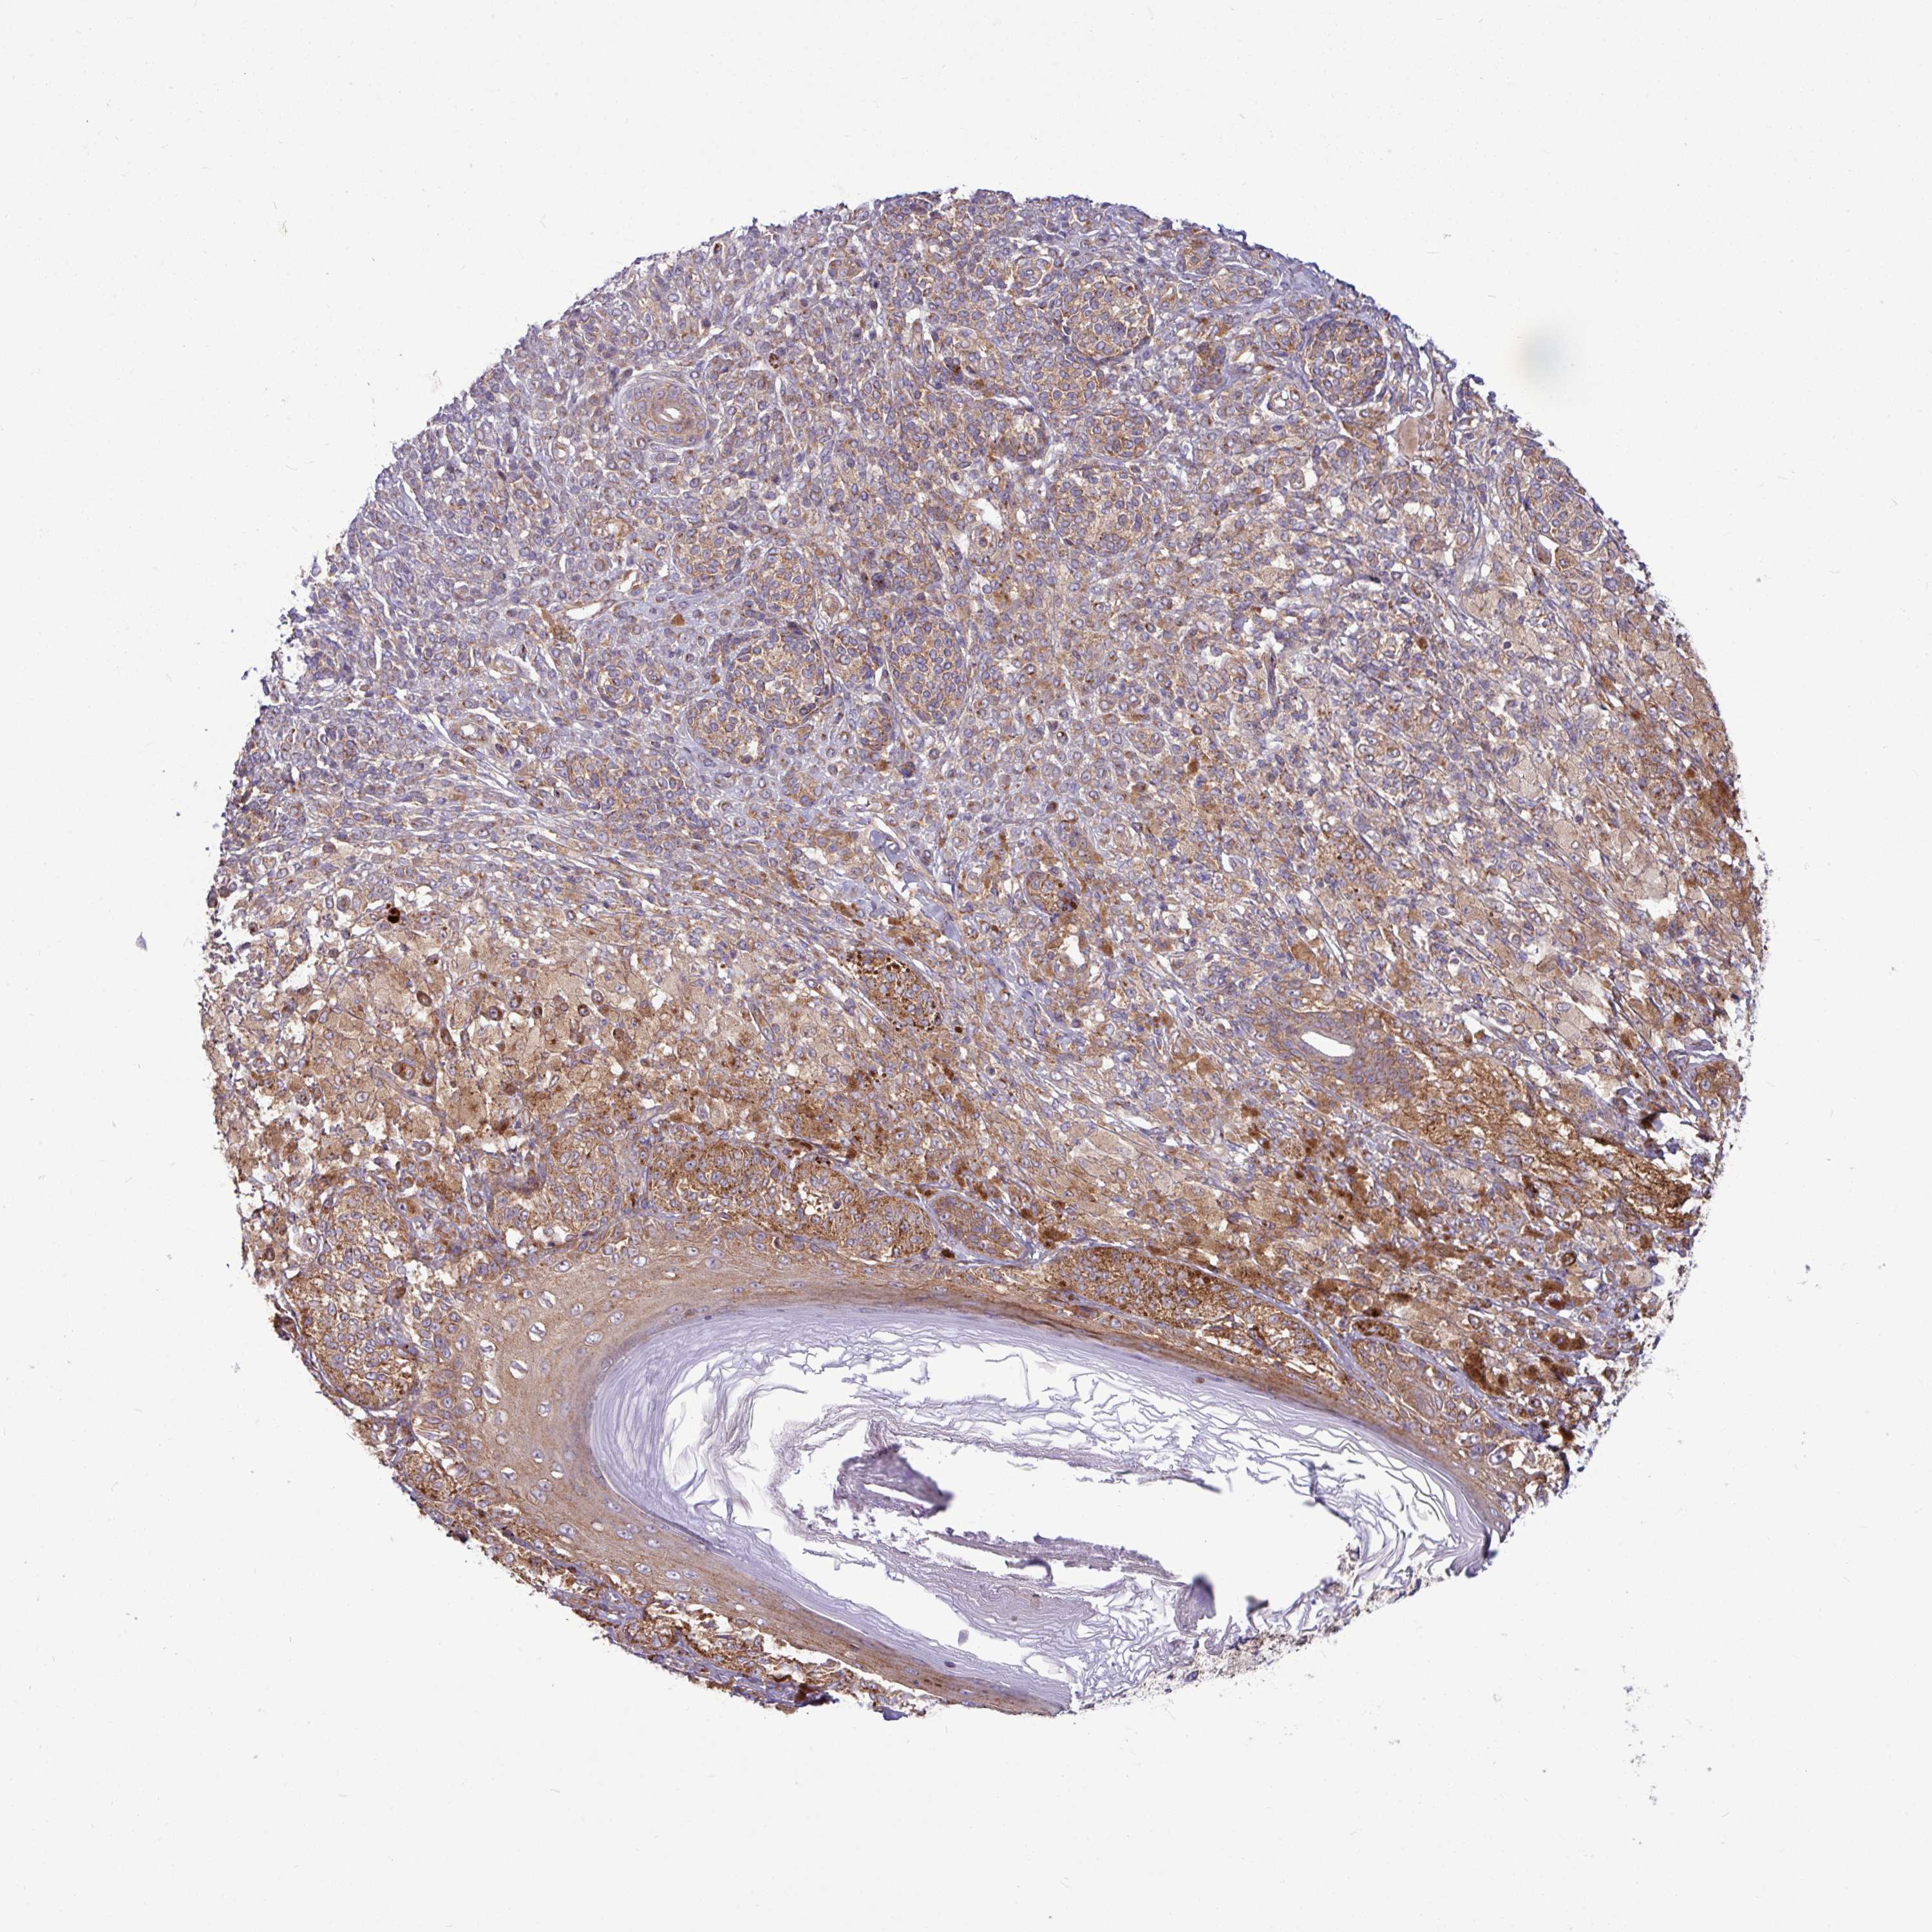

MELANOMA - Protein expressioni

A mouse-over function shows sample information and annotation data. Click on an image to view it in a full screen mode. Samples can be filtered based on level of antibody staining by selecting one or several of the following categories: high, medium, low and not detected. The assay and annotation is described here.

Note that samples used for immunohistochemistry by the Human Protein Atlas do not correspond to samples in the TCGA dataset.

Antibody stainingi

Antibody staining in the annotated cell types in the current human tissue is reported as not detected, low, medium, or high, based on conventional immunohistochemistry profiling in selected tissues. This score is based on the combination of the staining intensity and fraction of stained cells.

Each image is clickable and will lead to virtual microscopy that enables deeper exploration of all samples and also displays staining intensity scores, fraction scores and subcellular localization as well as patient and tissue information for each sample.

Antibody HPA051934

Staining

High

Medium

Low

Not detected

Intensity

Strong

Moderate

Weak

Negative

Quantity

>75%

75%-25%

<25%

None

Location

Nuclear

Cytoplasmic/membranous

Cytoplasmic/membranous,nuclear

Malignant melanoma, NOS